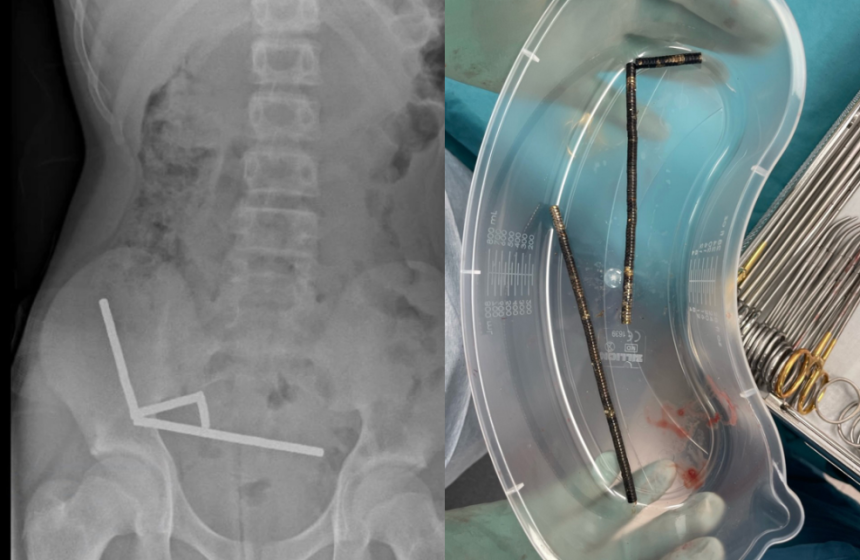

An X-ray shows lines of magnets in the boy’s abdomen. / Credit: New Zealand Medical Journal

Scans showed that the magnets had linked into four chains inside the teen’s bowel and at the start of his large intestine. The amount of magnets in his body disrupted some imaging, the report said, so doctors proceeded with an exploratory surgery.

The magnets removed from the boy’s abdomen. / Credit: New Zealand Medical Journal

During the operation, surgeons found the magnet chains were causing pressure necrosis in the bowel and large intestine. Pressure necrosis occurs when tissue dies because there is too much pressure on it for an extended period of time. The surgeons were able to successfully remove the magnets, and the boy recovered from the operation. He was discharged after eight days in the hospital, the report said.